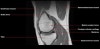

무릎 관절의 MRI 단면영상2016-08-31카테고리 106원본 보기1. Sagittal section 2. Coronal section 3. Axial section ← 이전 글전방 족근관증후군(Anterior tarsal tunnel syndrome) : 발등이 꽉 끼는 구두를 신은 후부터 발등을 누르면 아프고 엄지와 검지 발가락 사이가 저려요다음 글 →흉곽출구증후군(Thoracic outlet syndrome) : 팔이 아프고 감각이 떨어지면서 저려요같은 카테고리 글2017-06-10톰슨 검사(Thompson test) : 아킬레스건 파열을 조사하는 테스트2017-06-09Apley 압박 검사(Apley compression test) : 반월상 연골 손상을 조사하는 테스트2017-06-08맥머레이 시험(McMurray test) : 반월상 연골 손상을 조사하는 테스트← 전체 글로 돌아가기